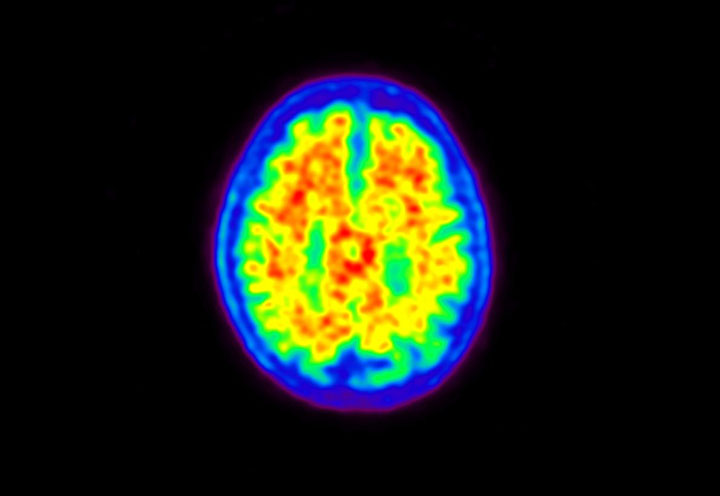

Head / Case5 : Amyloid

Courtesy : Kindai University Hospital

- Imaging protocol

- Injected dose: 4.27 MBq/kg, 18F-Flutemetamol

- Uptake time: 99 minutes

- Scan time: 20 minutes